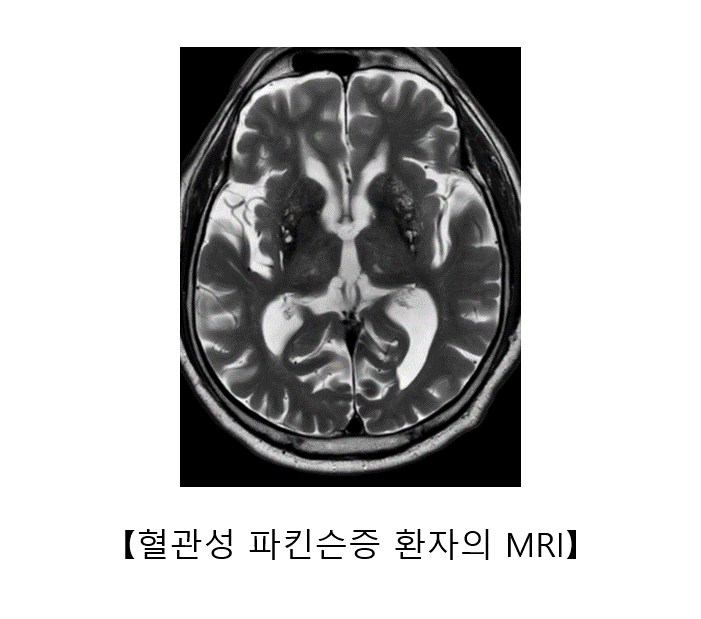

③ 혈관성 파킨슨증

혈관성 파킨슨증은 뇌의 기저핵이나 피질하 백질에 분포하는 작은 혈관들의 장애로 발생합니다. 갑작스럽게 발생하는 일반적인 뇌경색 증상과는 달리, 발음 이상, 운동 완만, 보행 장애, 인지 기능의 저하 등의 증상이 서서히 진행할 수 있습니다. 이 중 가장 두드러진 증상은 보행 장애로, 종종걸음, 동결 보행 등의 모습을 보입니다. 배뇨 장애도 흔히 동반됩니다.

혈관성 파킨슨증은 뇌 자기공명영상에서 뇌의 기저핵과 뇌실 주변에 허혈성 병변이 동반된 경우에 의심할 수 있습니다. 혈관 질환이 더 진행되지 않도록 항혈소판제를 투여하거나, 고혈압, 당뇨, 고지혈증과 같은 혈관성 위험 인자를 철저하게 관리하는 것이 중요합니다. 혈관성 파킨슨증은 레보도파에는 거의 반응하지 않는 것으로 알려져 있습니다.